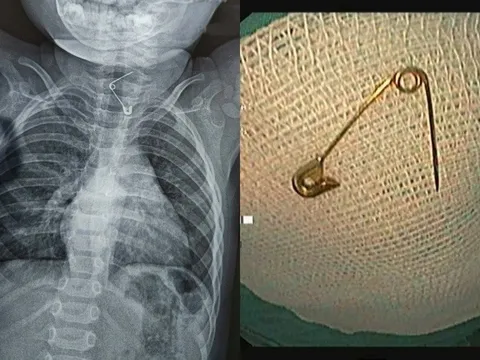

Bé 12 tháng tuổi nhập viện vì bị kim băng ghim thẳng vào thực quản: Bác sĩ cảnh báo 1 sai lầm nhiều cha mẹ mắc phải

Một bé trai 12 tháng tuổi đã phải nhập viện trong tình trạng khẩn cấp sau khi vô tình nuốt phải một cây kim băng sắc nhọn, dị vật này sau đó ghim thẳng vào thành thực quản, đe dọa nghiêm trọng đến tính mạng. Vụ việc một lần nữa là lời cảnh báo tới các bậc phụ huynh về mức độ nguy hiểm của những vật nhỏ, sắc bén trong tầm tay trẻ nhỏ.